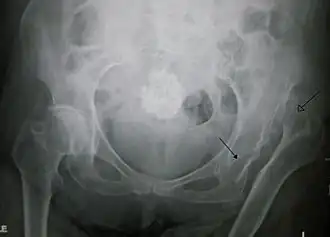

La luxation congénitale de la hanche est une affection du nouveau-né, symptomatique de dysplasie congénitale ou développementale de l'acetabulum.

Les anomalies chez le nouveau-né ou l'enfant connues sous le terme de dysplasie acétabulaire et subluxation ou luxation de la tête du fémur hors du cotyle (ou acetabulum), parce qu'ils sont présents à la naissance, sont longtemps étiquetées comme dysplasie ou luxation “congénitale” de hanche (Enseignement Hôpital Necker, Paris, Judet J. 1964)[source insuffisante].

Westin et al. (Westin GW, Ilfeld FW, Makin M et Paterson D., 1988)[source insuffisante] publient des observations de luxation “tardive” de hanche chez des enfants qui, nouveau-nés, ont un examen clinique et radiographique normal : ainsi naît le terme « dysplasie développementale de hanche » (DDH).